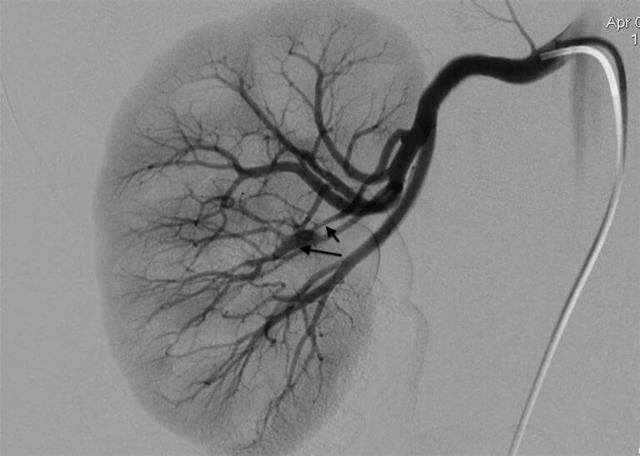

• Ангиография сосудов почек. Направлена на определение проходимости структур и степени нарушений кровотока.

Наиболее достоверным методом диагностики РВГ считается ангиография почечных артерий. С ее помощью можно определить происхождение патологического процесса, локализацию стеноза и его степень, что очень важно при вынесении решения о хирургическом вмешательстве.